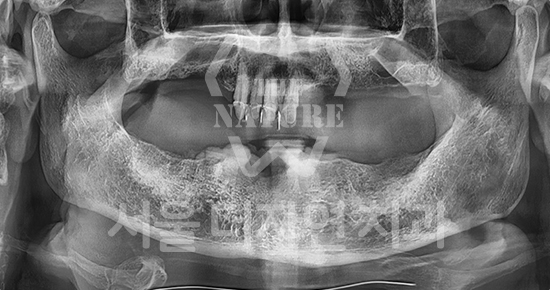

#Maxillary Bone Grafting

• BEFORE: 2021.11.02

• AFTER: 2022.01.19